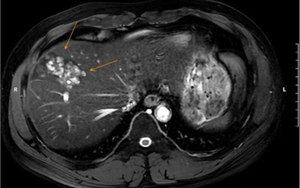

Nam bệnh nhân 41 tuổi, tại Hà Nội mới đây được phát hiện tổn thương gan nghiêm trọng do nhiễm sán lá gan lớn.